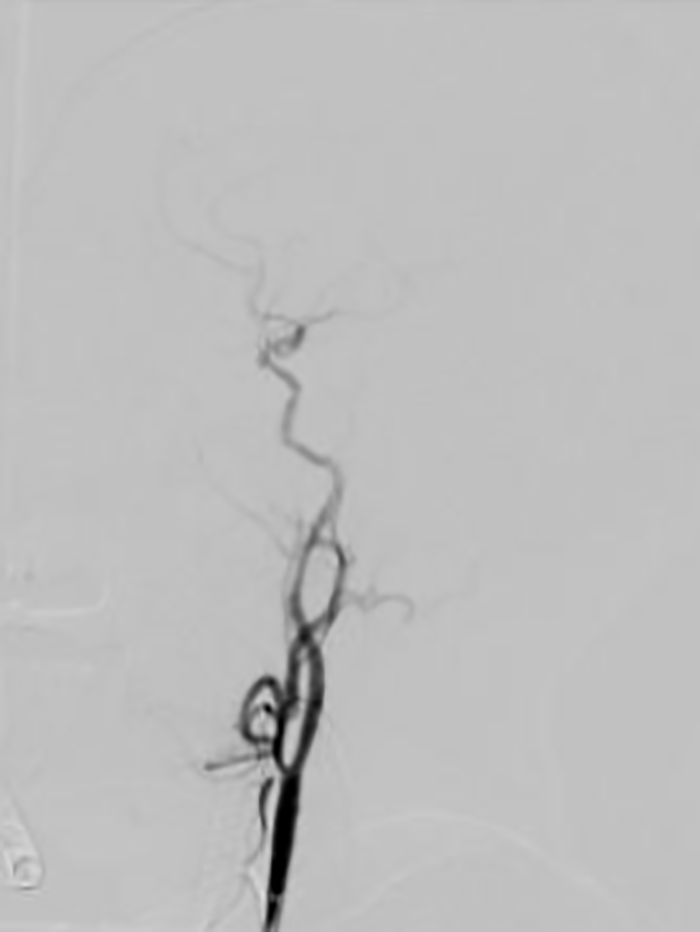

作为配合多年的老搭档,神经内科介入团队陈金龙主任医师、卢红腾主治医师与鲁红梅护士精细操作、密切协作,有条不紊地实施左侧颈内动脉窦部次全闭塞再通术(球囊扩张、支架置入)及左侧大脑中动脉取栓术。

经过两个小时的抢救,患者血管全部再通,手术取得成功!

▲患者术后脑血管完全再通